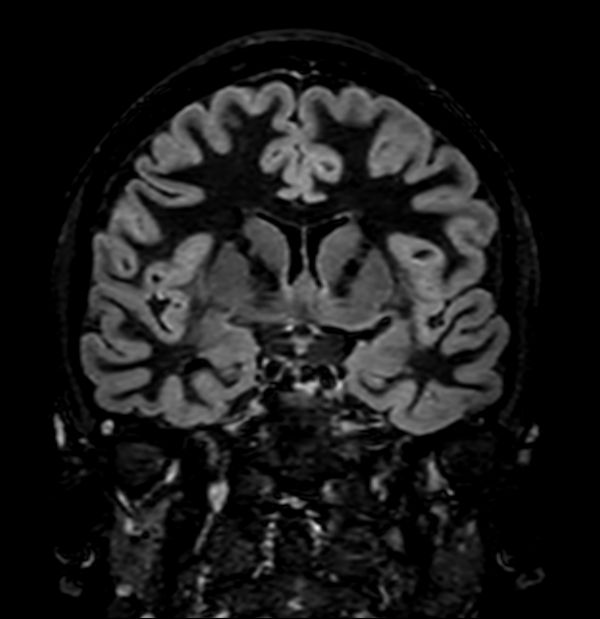

3D Double IR (Coronal reformat)

3D T2w TSE (Coronal reformat)